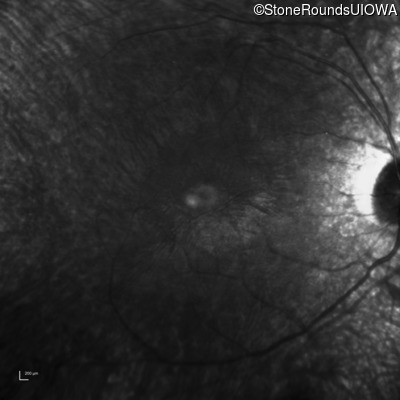

Age at visit: 19 years (Visit 2)

The clinical features favoring the diagnosis of retinitis pigmentosa with anisocytosis include: childhood onset periodic fever; mild anemia; anisocytosis on peripheral blood smear; night blindness and constricted visual fields as his earliest visual symptoms; bone-spicule-like pigmentation and narrowed arterioles on fundus examination; loss of outer retinal structures on OCT; and, normally sighted parents.